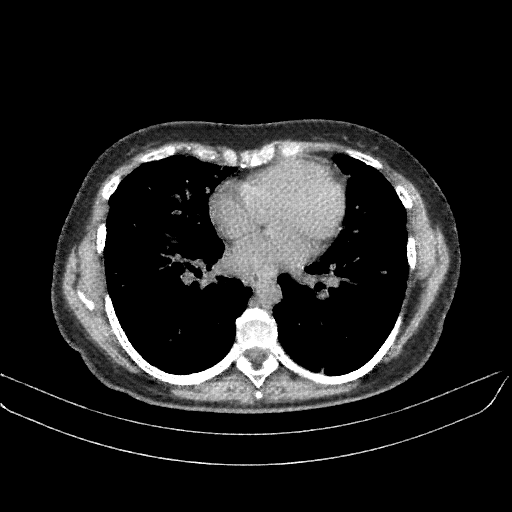

Generated VENOUS CT scan (A→B translation)

Lung window (WL -600, WW 1500 β†’ Low βˆ’1350, High +150)

Mediastinum window (WL 40, WW 400 β†’ Low βˆ’160, High +240)